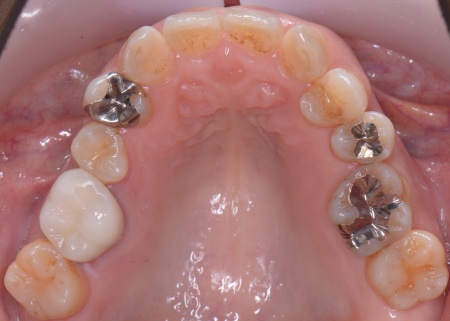

④矯正終了後に右上下奥歯の合わなくなった被せ物を除去し、自然な白さで強度もあるジルコニアセラミッククラウンを装着する。

最後に装着したジルコニアセラミッククラウンが歯に合っているか、噛み合わせに問題がないかを確認し、治療を終了しました。